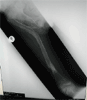

11 years old boy with long standing hip dislocation

Pre

Op

Xrays